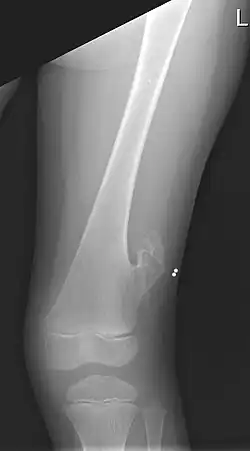

| X-ray of the left femur of a 5-year-old boy with an exostosis at the lateral side, just above the knee. | |

An exostosis, also known as a osteochondroma, is a benign chondrogenic lesion derived from aberrant cartilage from the perichondral ring.[1] Exostoses can cause chronic pain ranging from mild to moderate, but rarely severe, depending on the shape, size, and location of the lesion, though most are asymptomatic and are found serendipitously on plain x-ray taken for other reasons. It is most commonly found in pre-teens through early 20s adjacent to the physes of the distal femur and proximal tibia but can be found adjacent to other physes, most notably the distal phalanx of the finger, where it presents as a subungual mass. larger growths can occur on places like the ankles, knees, shoulders, elbows and hips. Very rarely are they on the skull. Though rare, malignant transformation can occur into a chondrosarcoma.